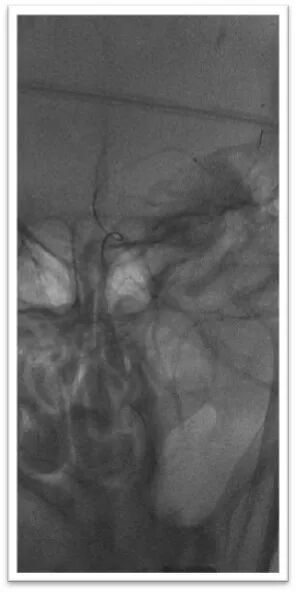

采用ADAPT技术长鞘直接抽吸

将6F Neuron Max长鞘抵近血栓近端后持续负压吸引抽出部分暗红色血栓,造影显示血栓完全栓塞颈总动脉分叉处,颈内动脉C1段可惨淡显影,由于路径迂曲长鞘长度受限,无法完全抵近血栓核心。